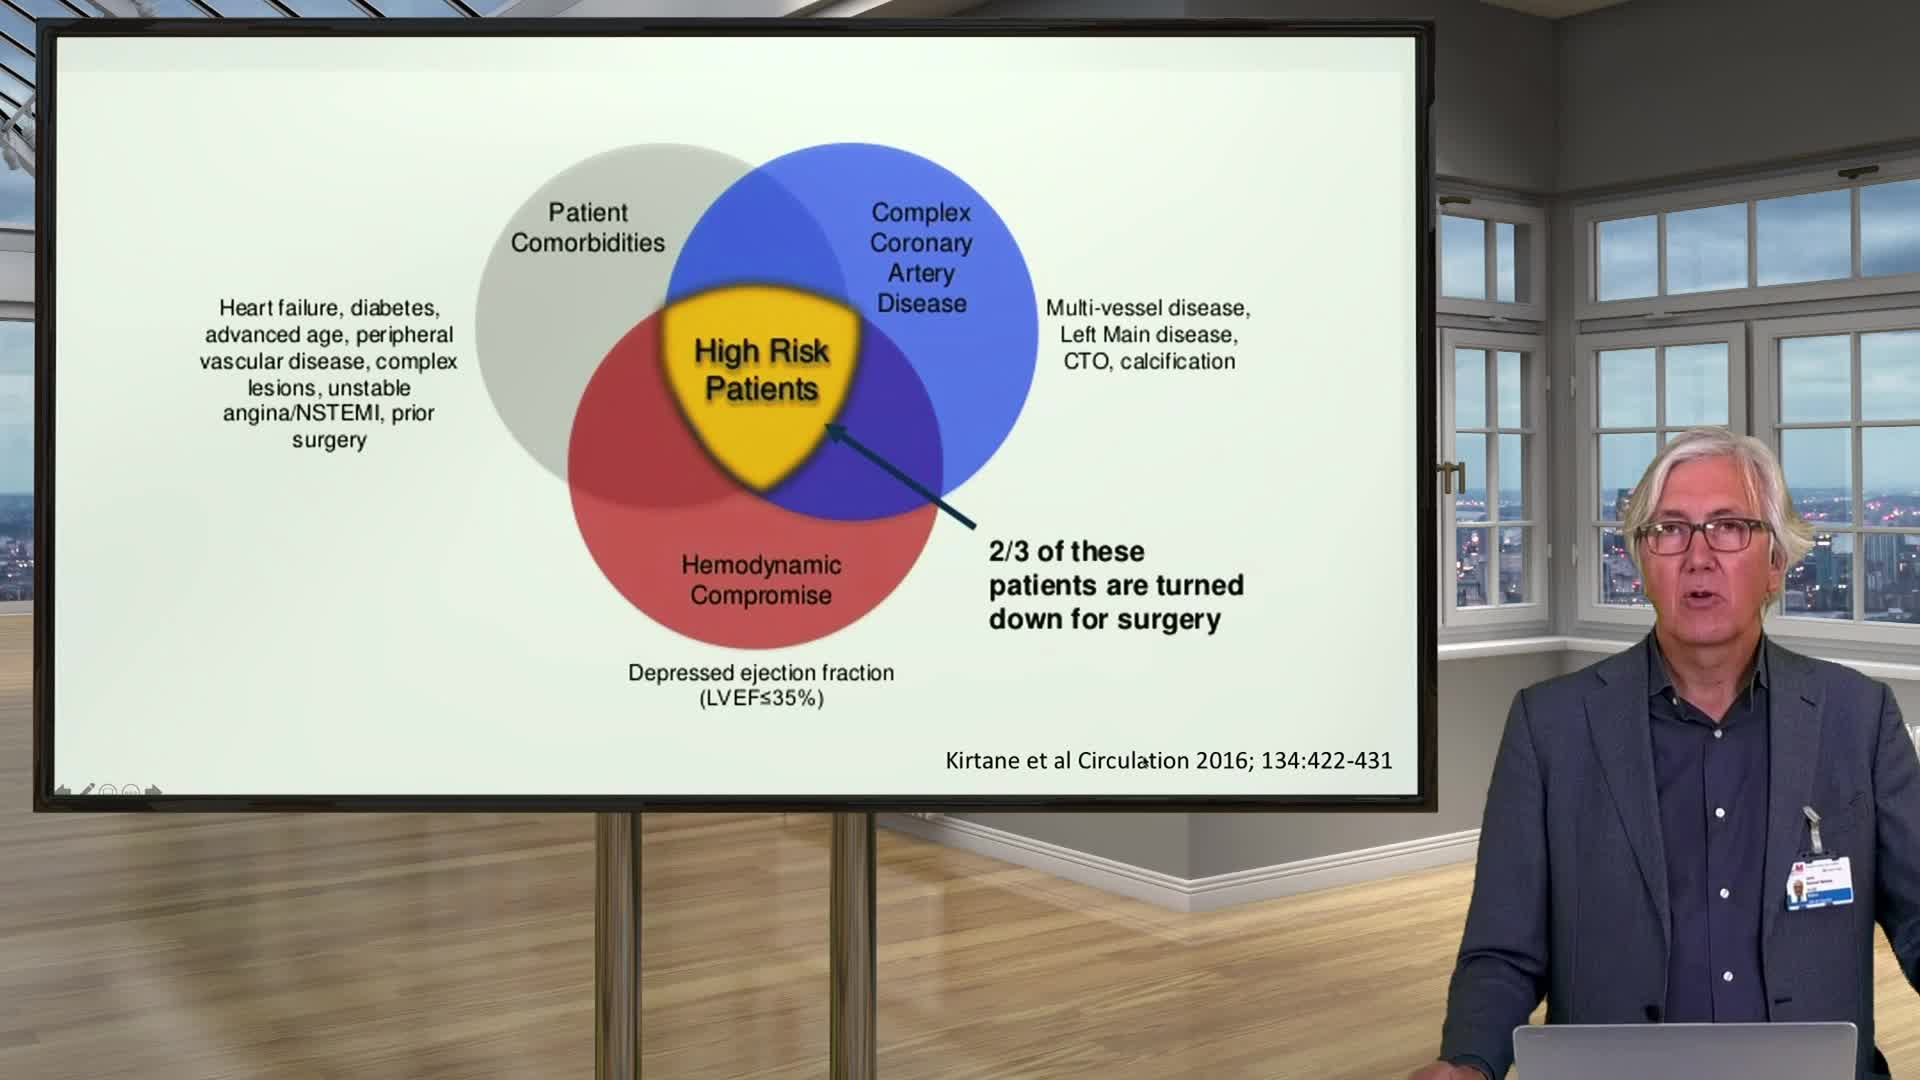

Ultralow Contrast PCI in complex and high risk patients - April 2024 Day One

Ultralow Contrast PCI in complex and high risk patients - April 2024 Day Two

Ultralow Contrast PCI in complex and high risk patients - November 2023 Day One

Ultralow Contrast PCI in complex and high risk patients - November 2023 Day Two

Ultralow Contrast PCI in complex and high risk patients - June 2023 Day One

Ultralow Contrast PCI in complex and high risk patients - June 2023 Day Two